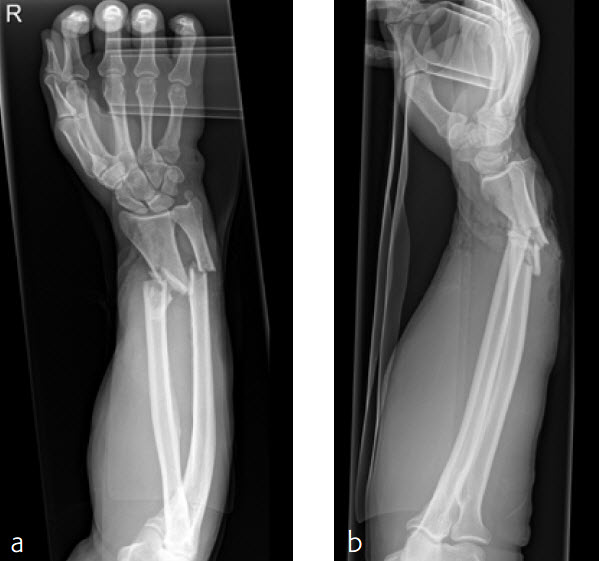

A 59-year-old farmer suffered a crush injury with an open forearm fracture (AO22 C2, Gustilo and Anderson IIIB) (Fig 5). Initial stabilization was carried out by external fixator (Fig 6). After four rounds of debridement and capillary ingrowth of a splitting skin graft at day 17, the VA LCP Extra Long Two-Column plate was used for fixation of the radius. A 2.7 mm LCP Condylar Plate was used for fixation of the ulna. The plates provided good stability for a functional after-treatment.